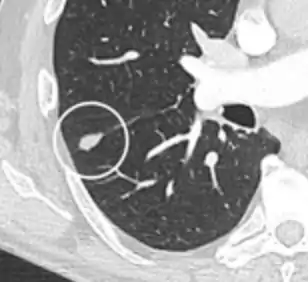

Calcifications and popcorn-like appearance, conferring a diagnosis of hamartoma.[9]

• In case of calcifications, a popcorn-like appearance indicates a hamartoma, which is benign.[3]